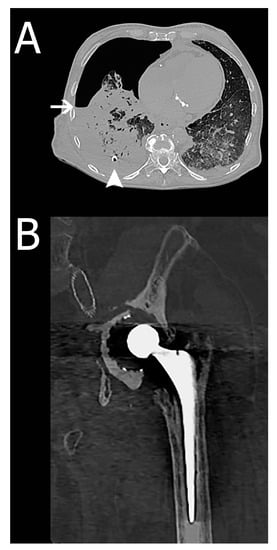

| False-negative of autopsy (type II error) | 38 | 3 | Hydropneumothorax, periprosthetic fracture, pneumatosis intestinalis. Two of these findings are illustrated in Figure 2. |